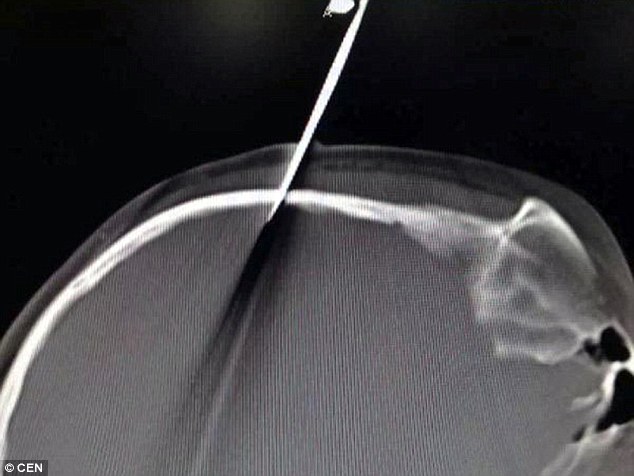

Μπροστά σε ένα απίστευτο θέαμα ήρθαν οι γιατροί σε νοσοκομείο της Κίνας που κλήθηκαν να εγχειρίσουν ένα 10χρονο κορίτσι όταν είδαν ότι στο κεφάλι του παιδιού ήταν καρφωμένο ένα ψαλίδι!

Ακόμα πιο απίστευτος ήταν το πώς καρφώθηκε το ψαλίδι στο κεφάλι του μικρού κοριτσιού καθώς ο πατέρας της είπε ότι συνέβη όταν του γλίστρησε την ώρα που της έκανε παρατήρηση επειδή δεν διάβαζε τα μαθήματά της.

Ο πατέρας της 10χρονης ισχυρίστηκε ότι ήθελε να τρομάξει την κόρη του επειδή εκείνη δεν διάβαζε αλλά έπαιζε.